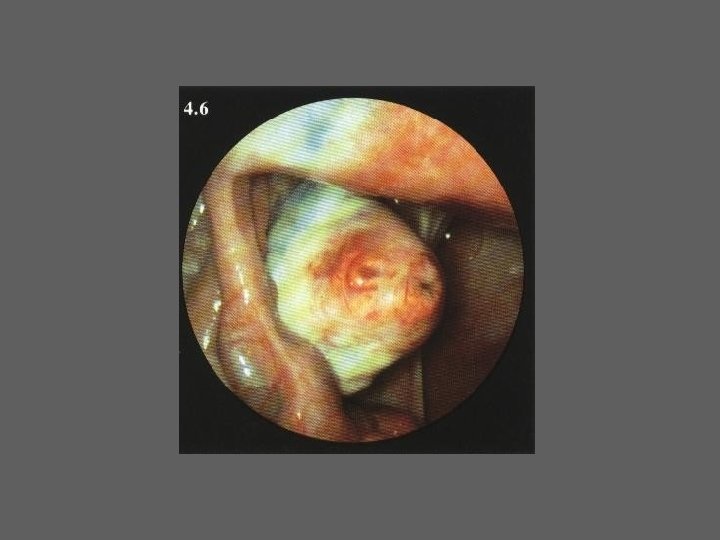

HISTEROSCOPIA - INDICAÇÕES Todas a situações em que se julgue vantajosa uma visualização completa da cavidade uterina, em particular: – Metrorragias – Dismenorreia adquirida – Infertilidade – Abortamentos de repetição e parto pré-termo – HSG anormal – DIU “perdido” – GIFT e ZIFT – Tratamento cirúrgico da patologia intracavitária: ● pólipos, miomas, septos, sinéquias, recessões endometriais ● baixos custos, reduzida morbilidade